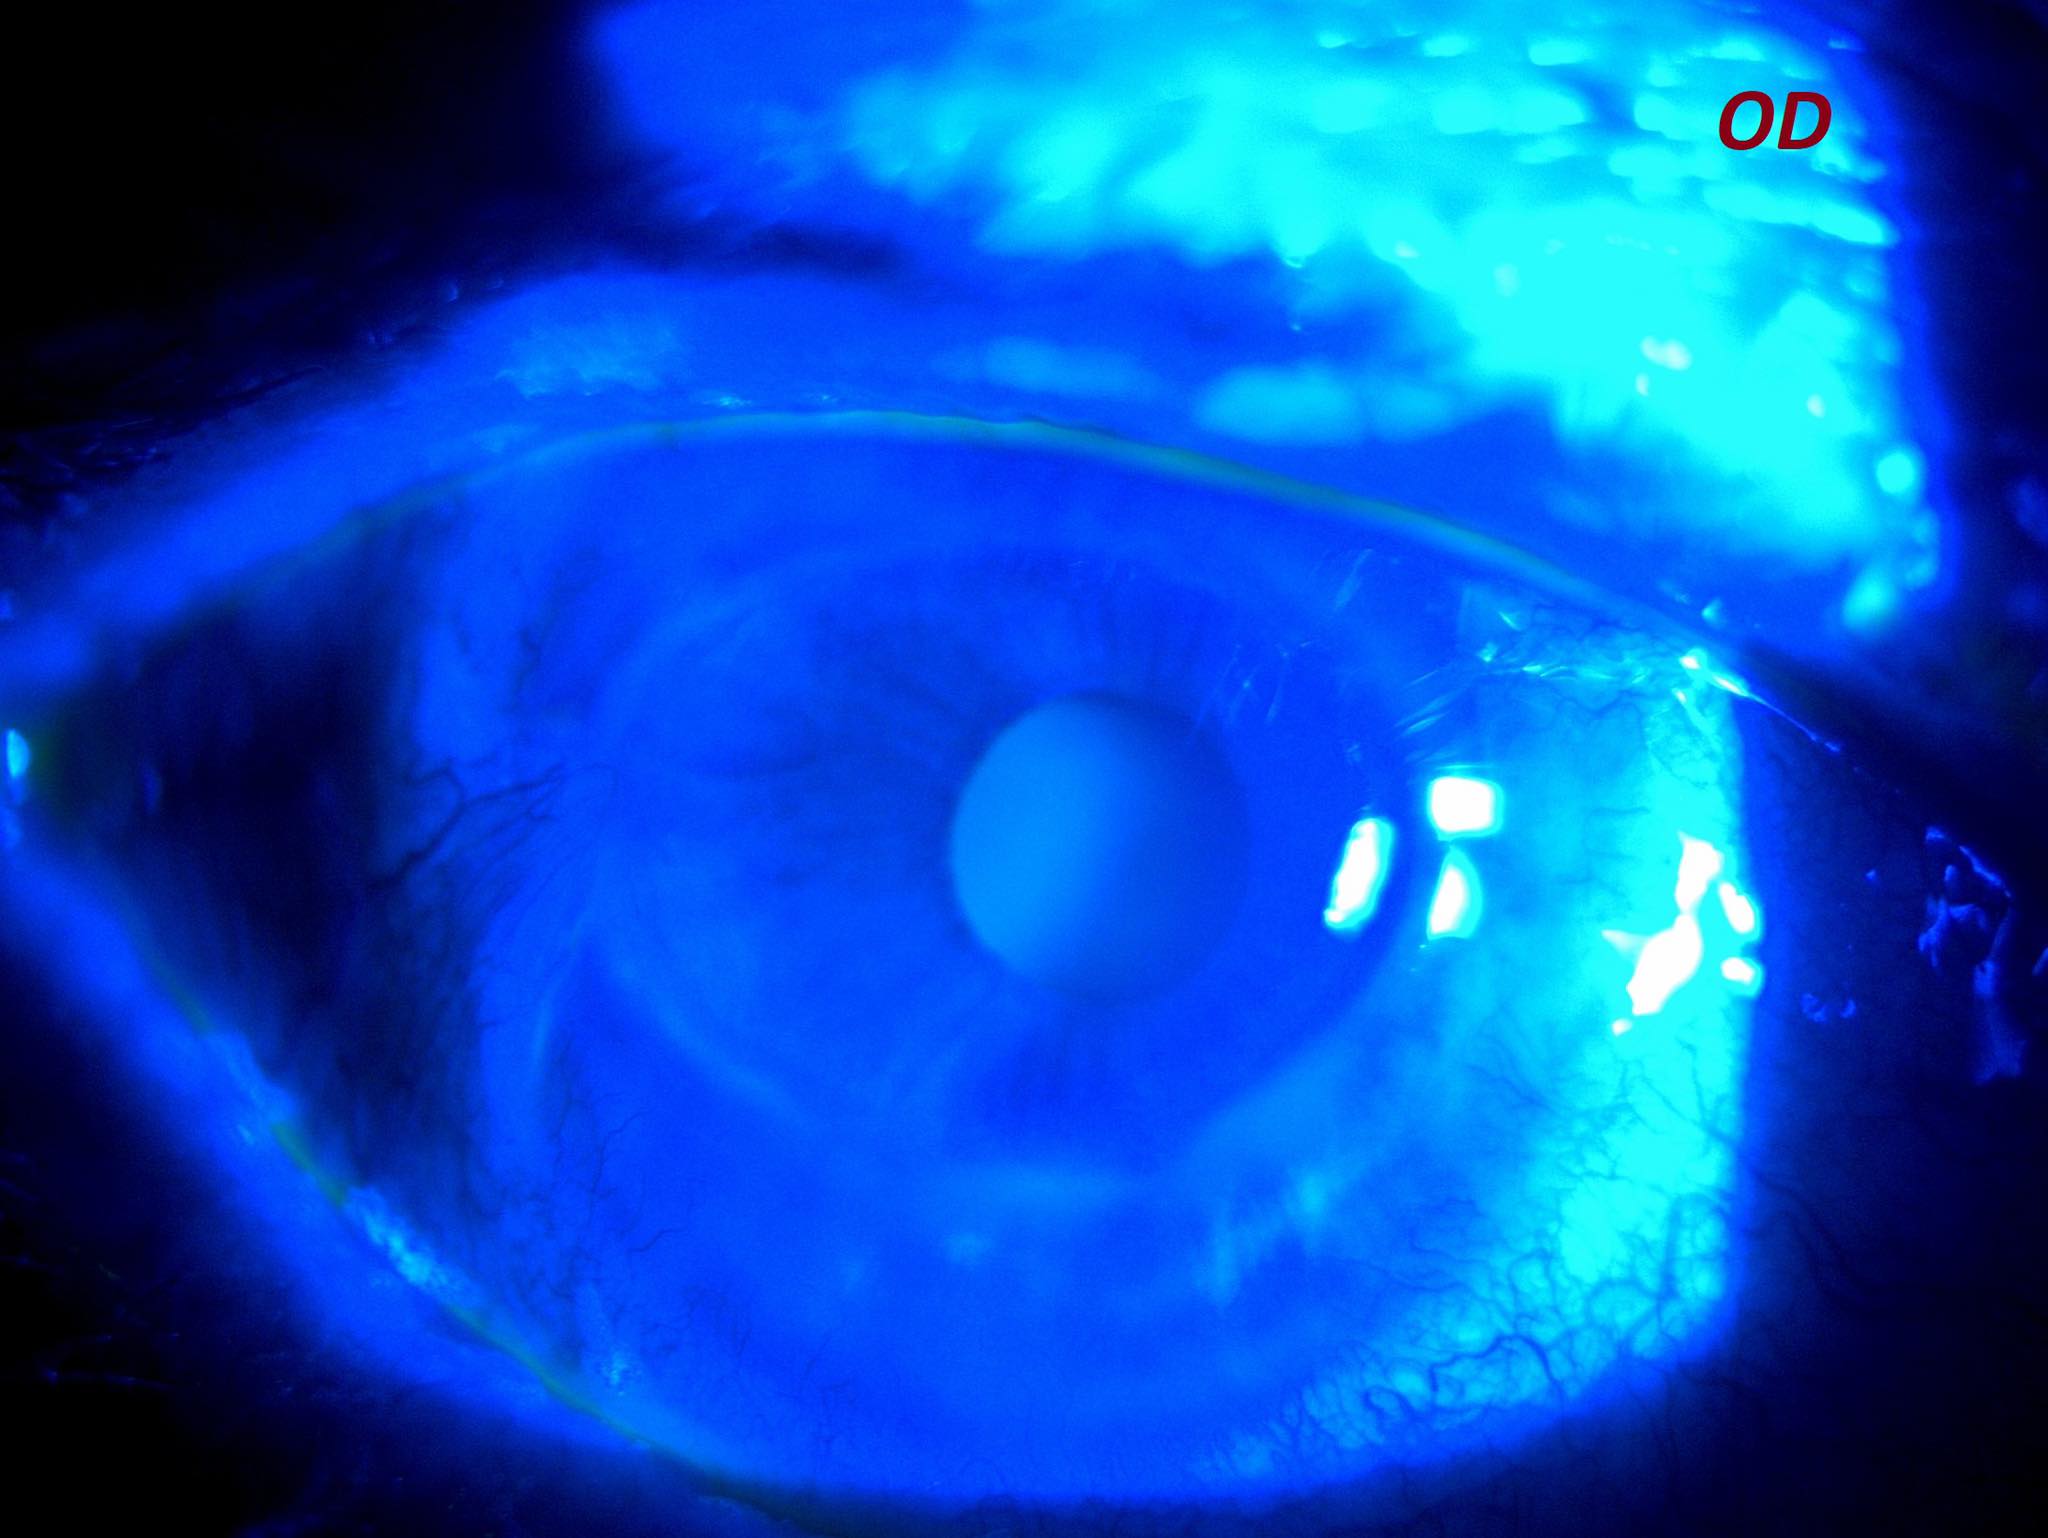

Această keratită a dus la subțierea extremă a corneei, cu deformarea ei neregulată, însoțită și de neo-vascularizație corneană periferică (apariția unor vase de sânge patologice, anormale, care nu-și au locul acolo), pe fond de sindrom de ochi uscat foarte sever (frecvent întâlnit în bolile autoimune).

Pe acest fond de cornee “anormală” a apărut și o cataractă foarte avansată, din cauza căreia pacienta noastră avea vederea foarte scăzută, sub 5% din standardul normal

Mai jos, câteva fotografii cu ambii ochi înainte de operație, urmate de două fotografii din timpul operației și ultimele două poze sunt ale ochiului operat, prima zi după operație.